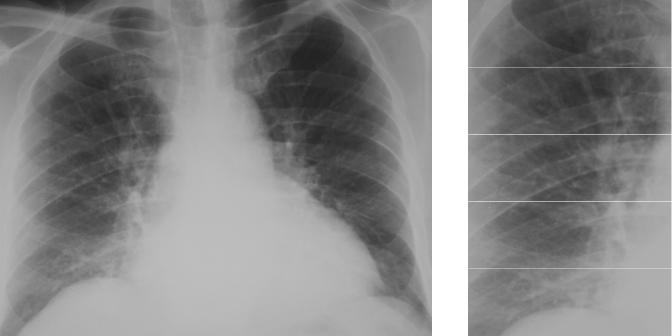

Фотографии, демонстрирующие обнаруженное усиление легочного рисунка

Раздел: Фотодневник открытий